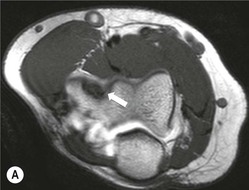

In acute injuries MRI shows the presence of soft-tissue oedema and haemorrhage around the affected ligament. MR arthrography may be preferred for diagnosis of chronic tears. Acute ulnar collateral ligament (UCL) tears often occur at the proximal origin on the medial humeral epicondyle (Fig. 46-23). In chronic tears the defect is usually at the insertion on the sublime tubercle of the ulna.14